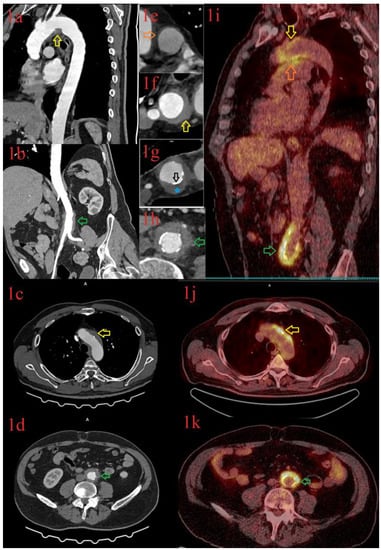

3.1.1. Patient 1